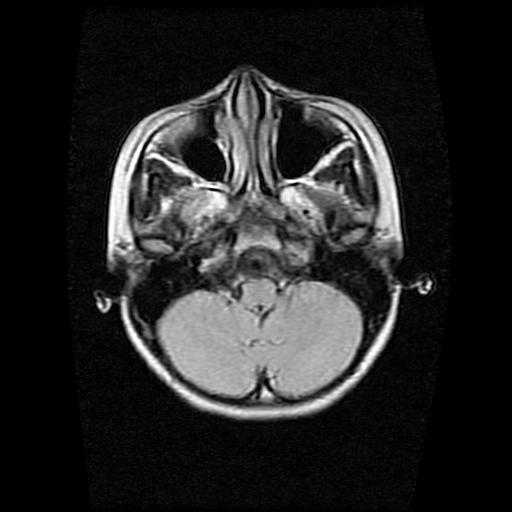

9岁女孩,三岁时诊断为癫痫,一直服丙戊酸钠,现患者一般情况良好,家长复查核磁片,看能否停药..

巨脑回

未见异常信号灶.

停药要结合临床,如无发作可以停。